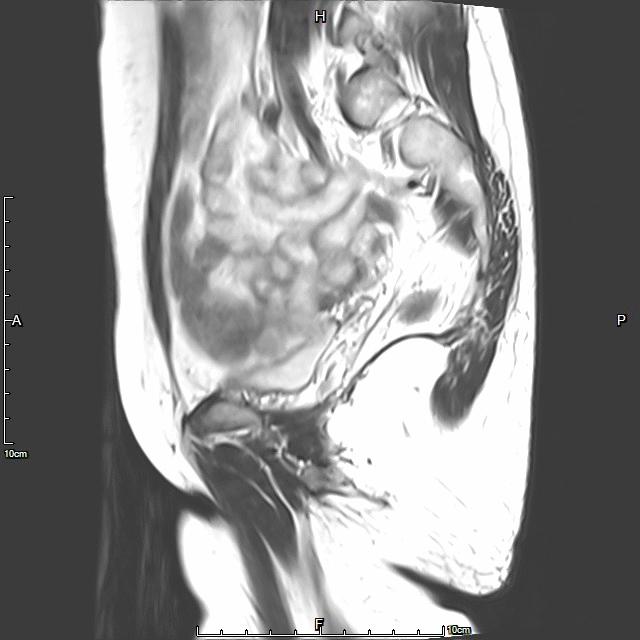

• 术前MRI检查显示子宫明显增大。

术前MRI检查显示子宫明显增大